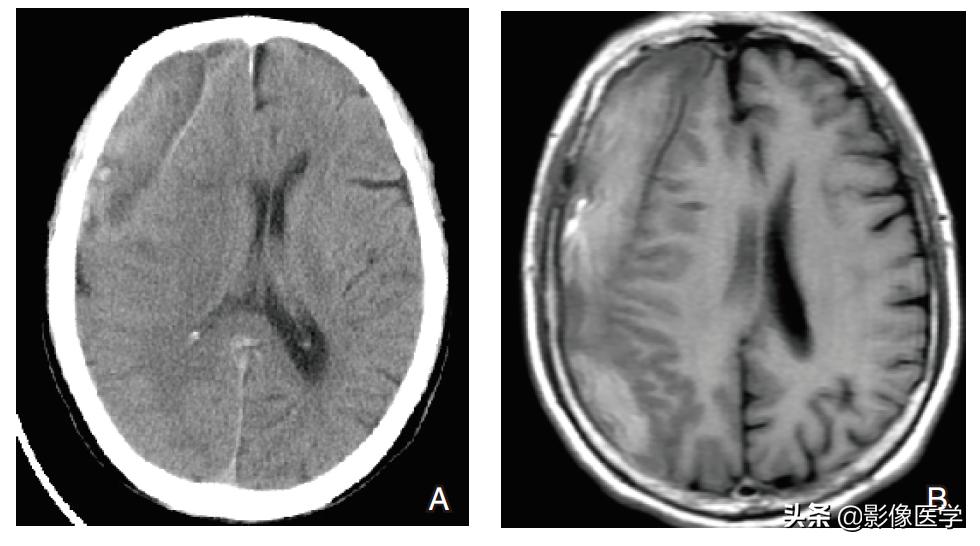

case(3)

【病史】男性,68岁。间断性头痛头晕6月入院。

【影像学检查】头颅CT和MRI检查:

【影像学表现】头颅CT平扫(图A)右侧颅骨内板下方见新月形低等高混杂密度影,边界清楚,邻近脑实质受压内移,右侧脑室受压变形,中线结构向左侧移位。MRI平扫T1WI(图B)、T2WI(图C)及DWI(图D)示右侧额顶部病灶在T1WI上呈等高混在信号,T2WI上呈低等高混杂信号,DWI弥散未见受限。

【影像学诊断】右侧额顶部慢性期硬膜下血肿。

【最后诊断】右侧额顶部慢性期硬膜下血肿。